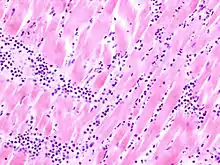

Mikro: Interstitielles lymphozytäres Infiltrat (kleine blaue Zellen), kaum Nekrosen.

![]() Virale Myokarditis bei Patient mit plötzlichem kongestiven Herzversagen, Autopsiepräparat, H&E. |

![]() idem. |